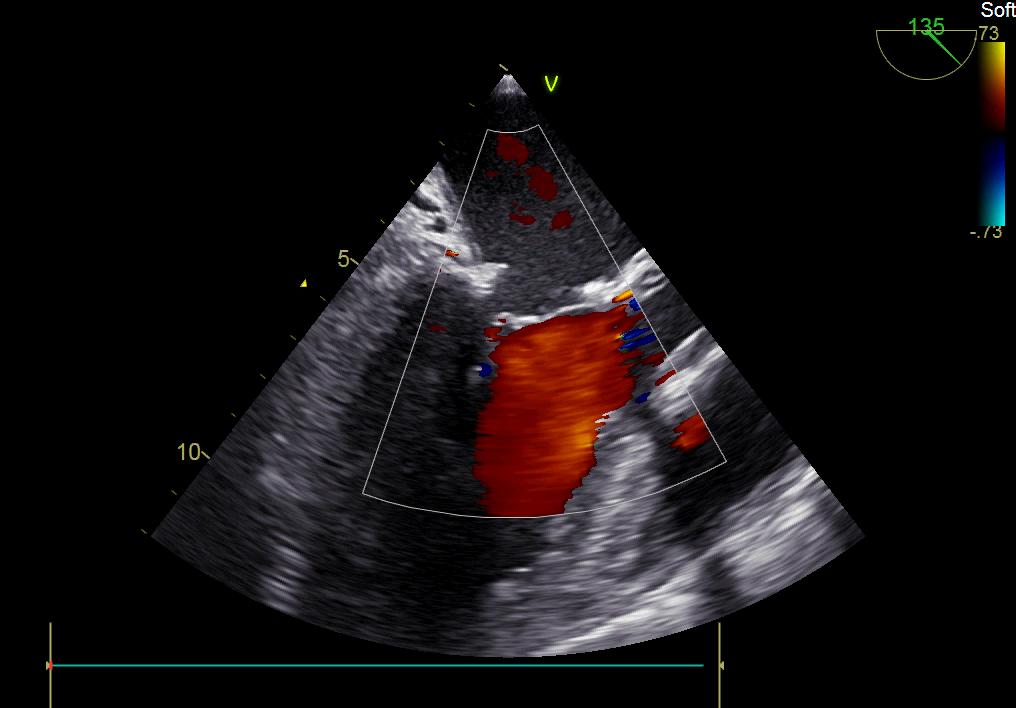

患者何某,42歲男性,因心功能不全入住我院心胸外科,心臟彩超提示二尖瓣后葉脫垂伴有重度返流及心臟擴(kuò)大,在迅速糾正心衰后,手術(shù)便提上日程,心胸外科廖金文主任多次組織全科及兄弟科室討論,在二尖瓣置換及成形術(shù)上,最終決定采取二尖瓣成形術(shù)。為保證手術(shù)安全,討論圍手術(shù)期各個(gè)細(xì)節(jié),所謂細(xì)節(jié)決定成敗,因?yàn)樾g(shù)前的細(xì)致全面,加上術(shù)中的一絲不茍及術(shù)后的精細(xì)化管理,患者術(shù)后恢復(fù)順利,健康出院,復(fù)查心臟彩超未見(jiàn)二尖瓣返流。

術(shù)后彩超